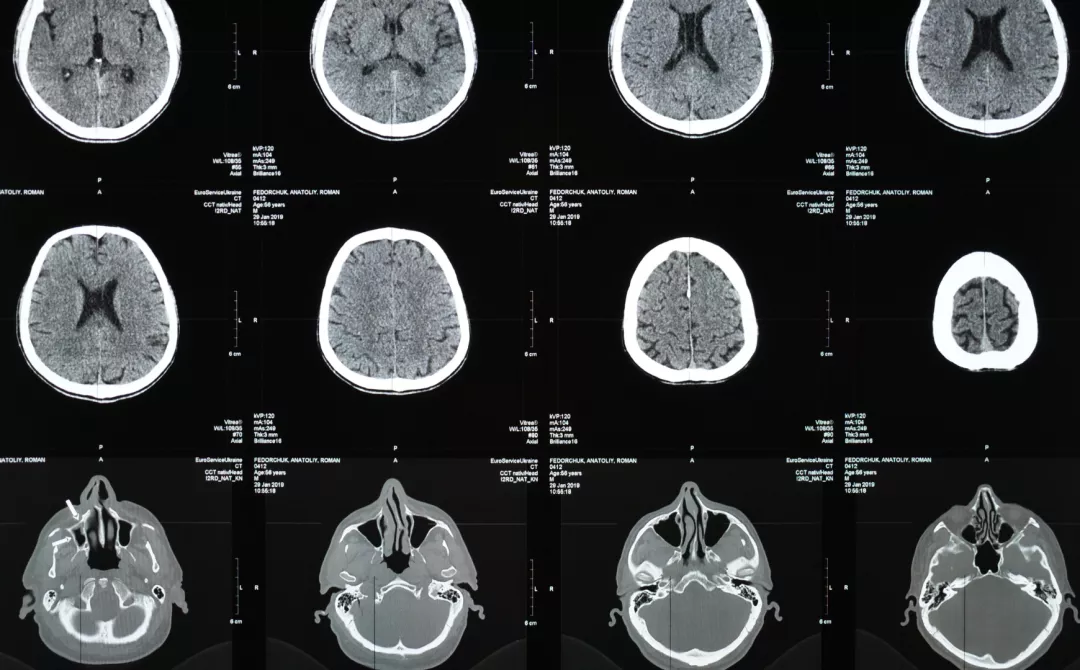

Image

Illustration of central nerve system

Illustration of brain MRI scans